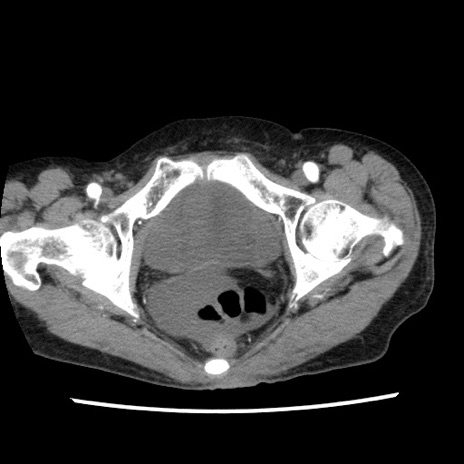

冠状断像

矢状断像